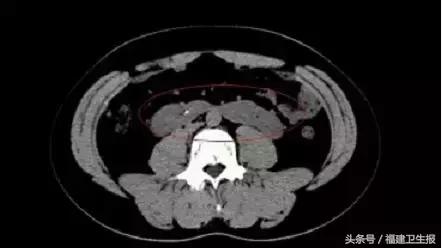

泌尿系CT显示,小刘两肾下极融合部即峡部横过主动脉前方, 肾盏位于肾前方,输尿管越过峡部两侧前方下行,是一位马蹄肾泌尿结石患者。

△小刘的CT图显示肾脏下级相互连